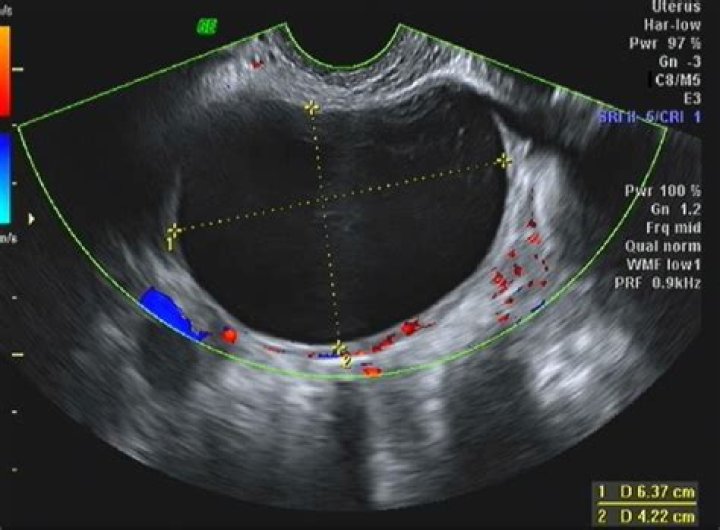

What is simple right adnexal cyst?

A simple cyst is a round or oval anechoic fluid collection with smooth thin walls, no solid component or septation, and no internal flow by using color Doppler imaging (Fig 1). When describing cysts in the pelvis, we use the term adnexal if the cyst is not clearly arising from the ovary.

What is considered a large adnexal mass?

If an adnexal mass larger than 6 cm is found on ultrasonography, or if findings persist longer than 12 weeks, referral to a gynecologist or gynecologic oncologist is indicated.

Is an adnexal mass a cyst?

Adnexal masses are characterized on ultrasonography as cystic, solid, or complex. According to an American College of Radiology guideline, simple cysts in premenopausal women are considered benign. 11 Complex masses may rarely be malignant in premenopausal women.